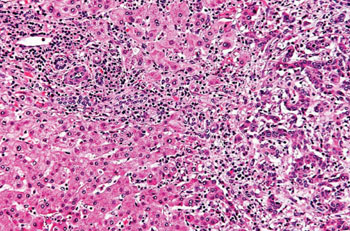

Гистопатология грудной холангиокарциномы, или опухоли Клатскина (фото любезно предоставлено Nephron).